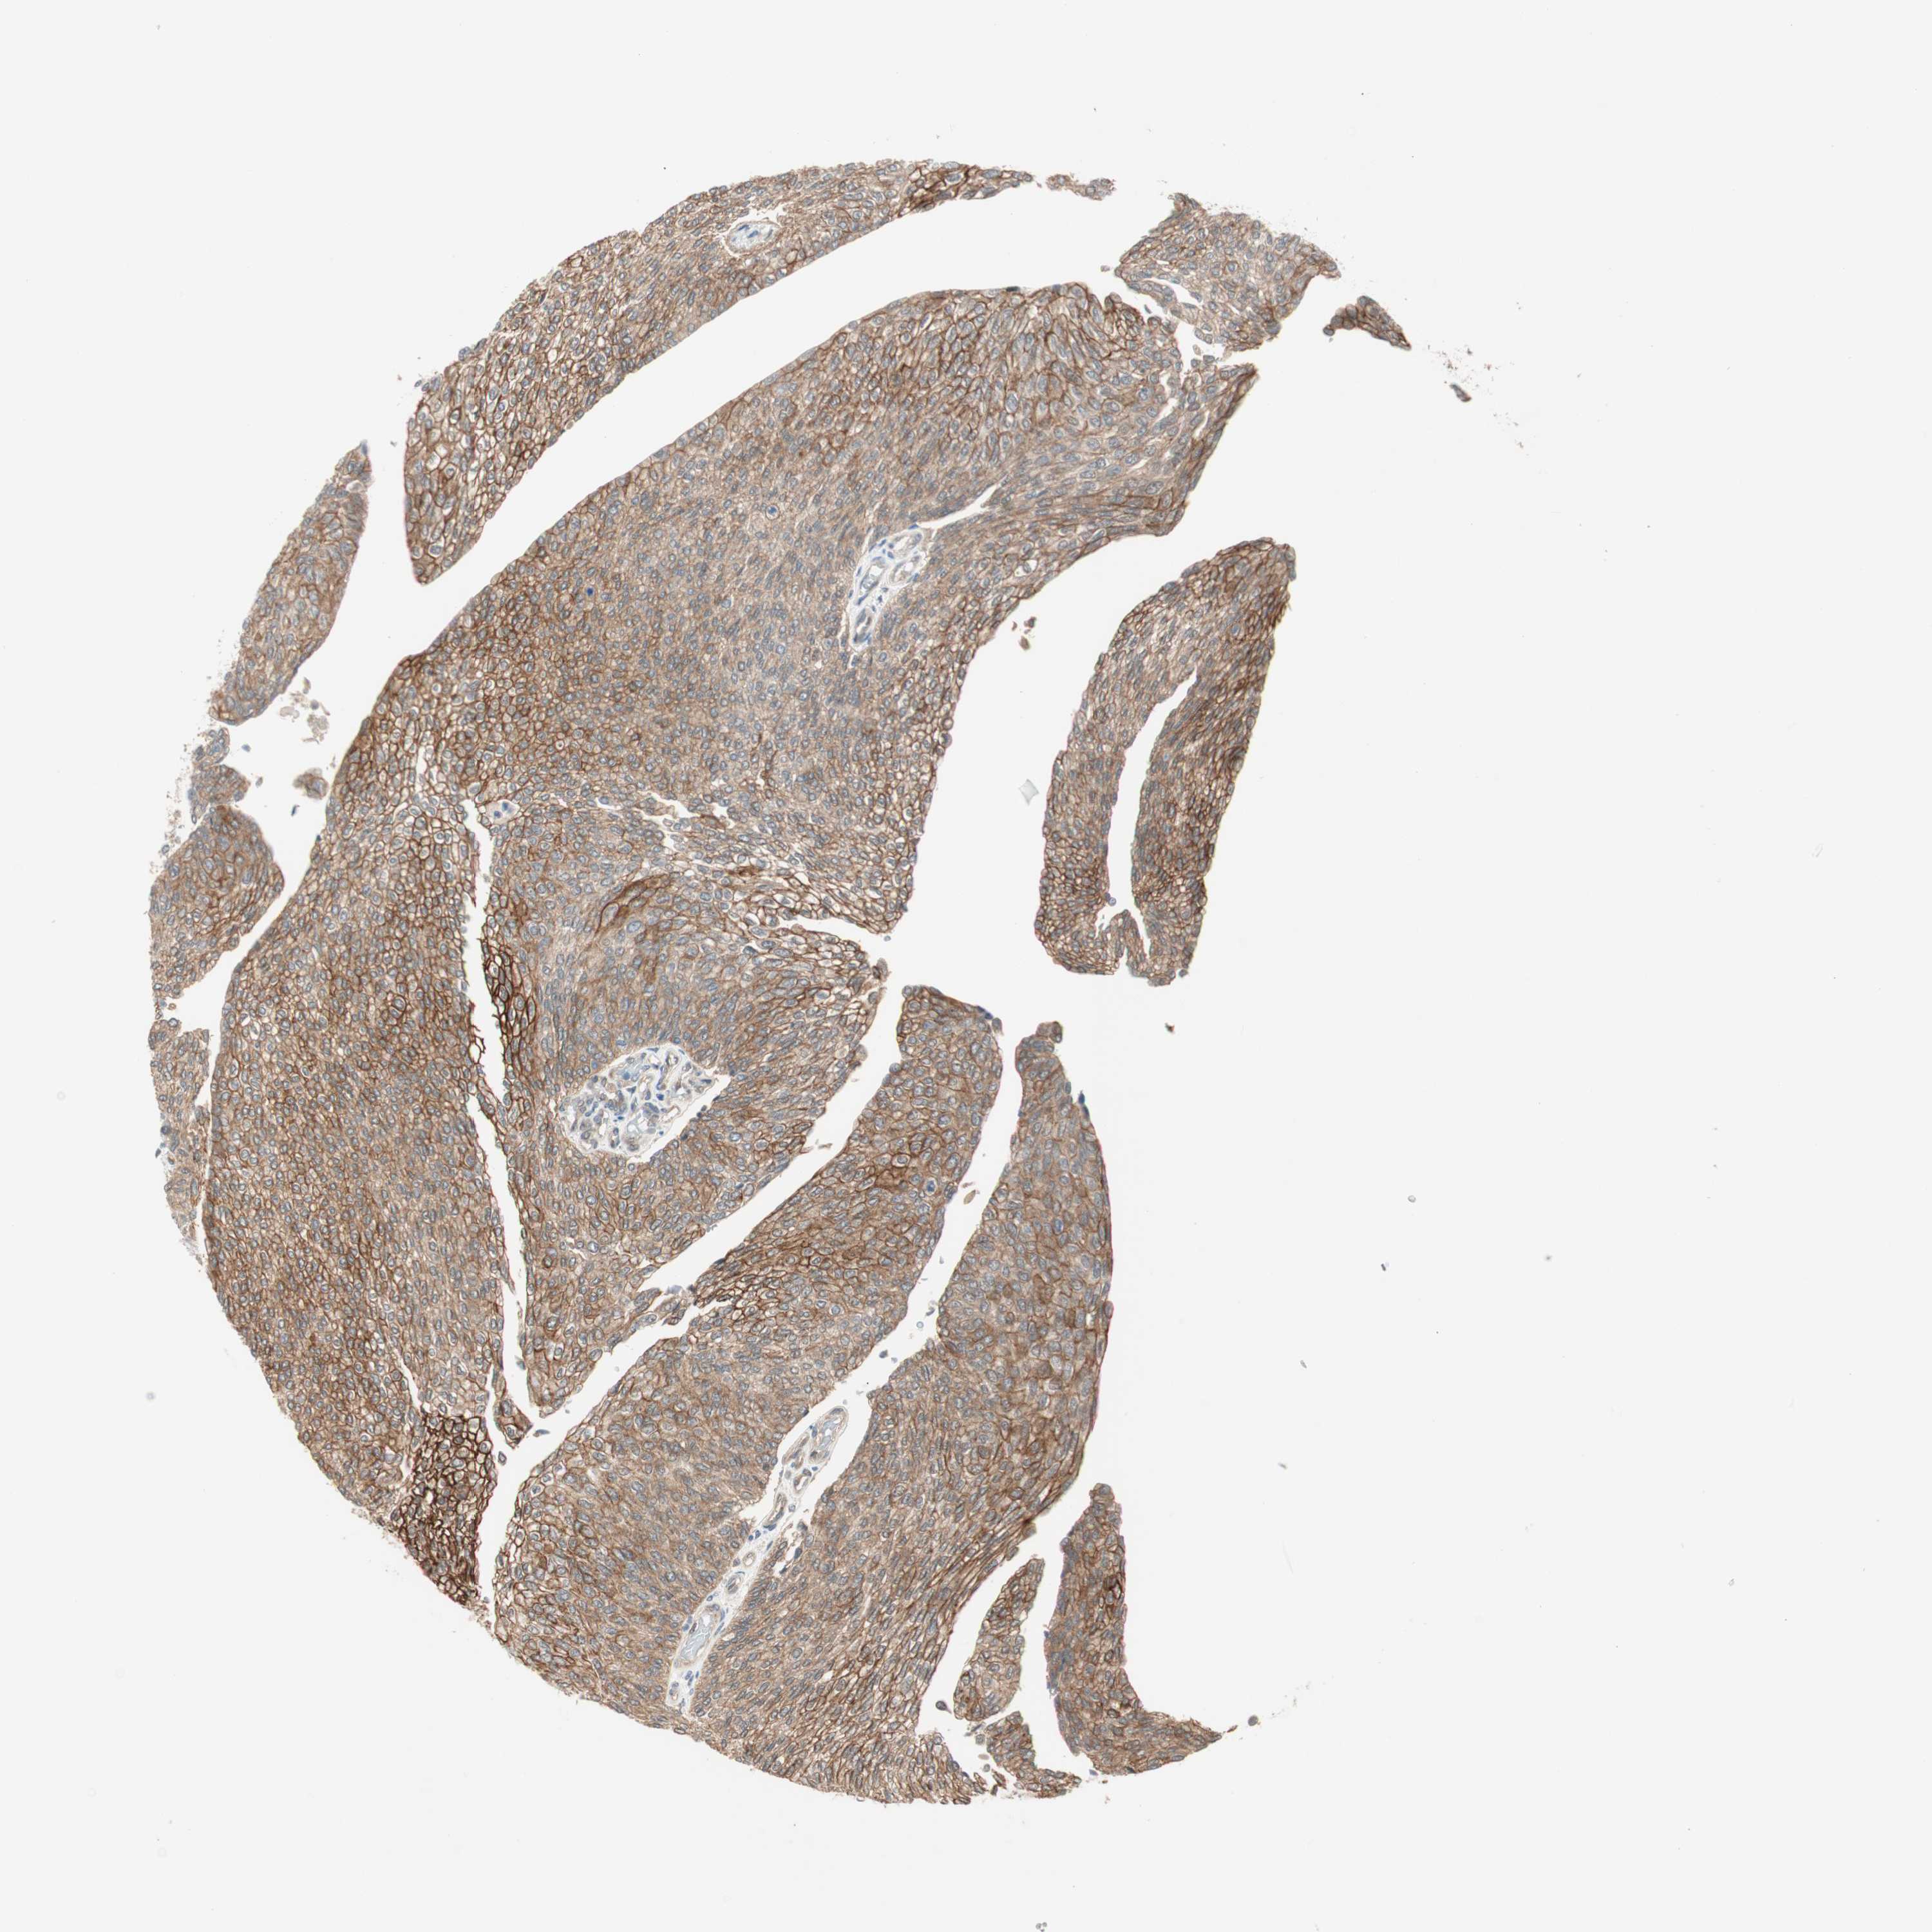

UROTHELIAL CANCER - Protein expressioni

A mouse-over function shows sample information and annotation data. Click on an image to view it in a full screen mode. Samples can be filtered based on level of antibody staining by selecting one or several of the following categories: high, medium, low and not detected. The assay and annotation is described here.

Note that samples used for immunohistochemistry by the Human Protein Atlas do not correspond to samples in the TCGA dataset.

Antibody stainingi

Antibody staining in the annotated cell types in the current human tissue is reported as not detected, low, medium, or high, based on conventional immunohistochemistry profiling in selected tissues. This score is based on the combination of the staining intensity and fraction of stained cells.

Each image is clickable and will lead to virtual microscopy that enables deeper exploration of all samples and also displays staining intensity scores, fraction scores and subcellular localization as well as patient and tissue information for each sample.

Antibody HPA006702

Antibody CAB021101

Staining

High

Medium

Low

Not detected

Intensity

Strong

Moderate

Weak

Negative

Quantity

>75%

75%-25%

<25%

None

Location

Nuclear

Cytoplasmic/membranous

Cytoplasmic/membranous,nuclear

Urothelial carcinoma, High grade